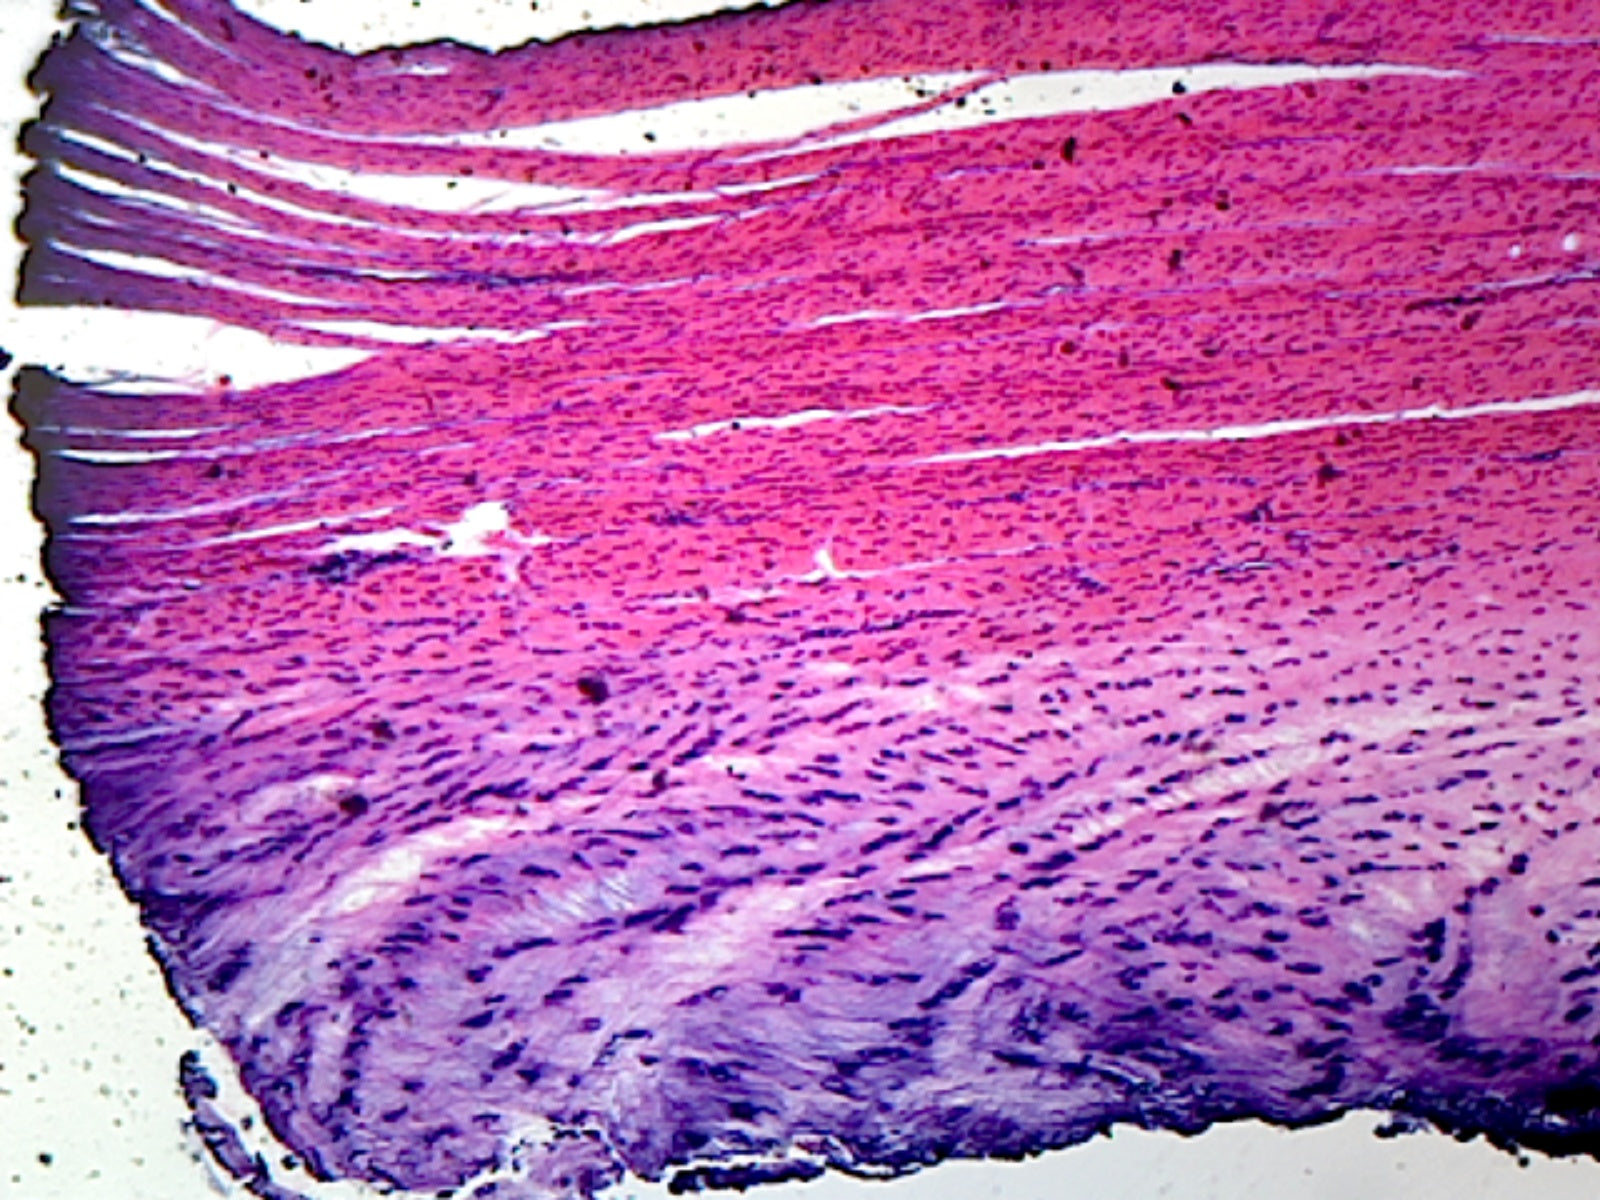

This slide is a section of white fibrocartilage taken from the intervertebral disc of a mammal.